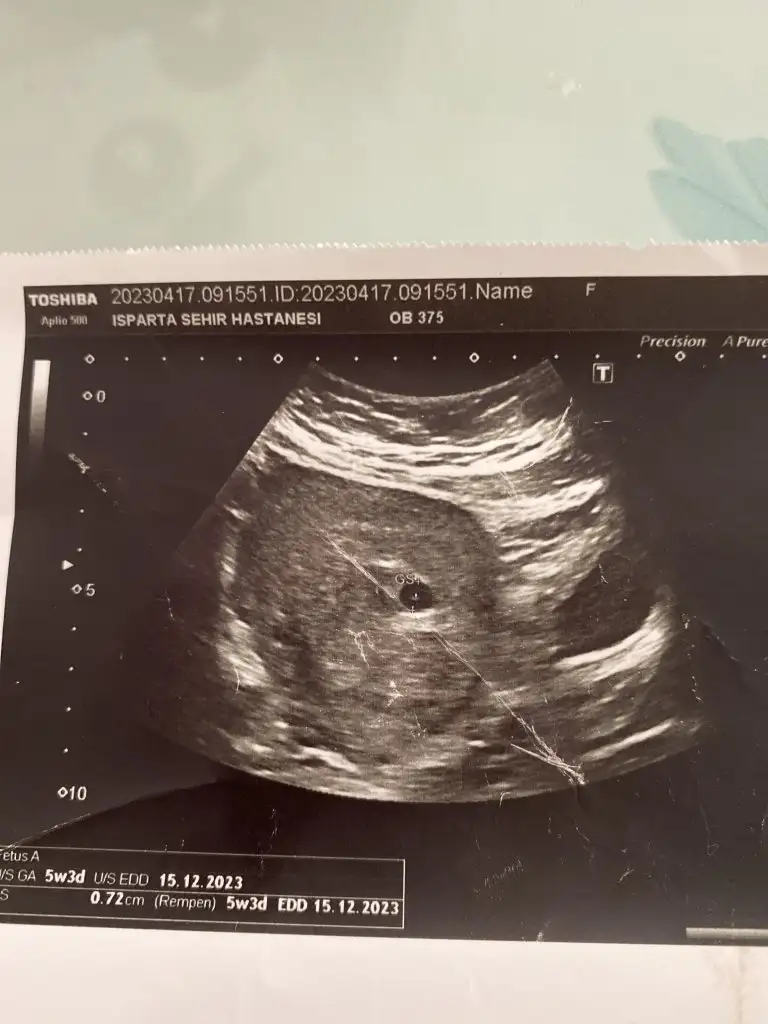

Herkese günaydın. Ben dün ikili test sonucumu almaya gittim, gitmişken de muayene olayım dedim bebek duruyor mu diye

doktor o sırada bir şeyle meşguldu, asistanı baktı, sekreteri de bilgisayardan asistana okudu riskleri. Yaş riski hariç düşük çıktı (yaş 1/59, down 1/1035 trisomi 18 13 1/300000 civarı). Güzel dediler (yaştan dolayı zaten fetal yaptıracağımı biliyorlardı) sonra sonucu istedim ama devlet hastanesi olduğu için yazıcıya gönderiyorlar, çıkarken alıyorsunuz bankodan. Alınca kan değerlerimin birinin yüksek olduğunu fark ettim. Serbest beta hcg 2.33 mom (papp-a mom 1.84) çıkmış ve doktorla konuşma şansım olmadı hiç (muayene sırasında riskler konuşuldu sadece kan değerlerini okumadı sekreter, gündeme gelmedi yani), bugün fetal için kan vereceğim ama geceden beri sözelci-dilci halimle tıp makalelerini tarıyorum (kimi 1.5 mom üstü kimi 2.5mom üstü yüksek kabul ediyor ve down olasılığına ek olarak preeklamsi, hipertansiyon vb gibi birçok gebelik komplikasyonuna işaret edebileceği söyleniyor, çoğu bulgu papp düşük bu yüksekse sorun diyor ama atipik bulgular da büyük bir oranı oluşturuyor vb.) şu aşamada burada böyle bir deneyimi olan yoktur muhtemelen ama yine de belki bir fikri olan vardır diye yazmak istedim. Bir de kombine risk, biyokimyasal risk vb hesaplanmamış hiç. Acaba riskleri hesaplarken kan değerlerini dahil etmediler mi demek oluyordur bu? Fetal için kan vereceğim bugün ama sonucu bekleyebilir miyim bilemedim.